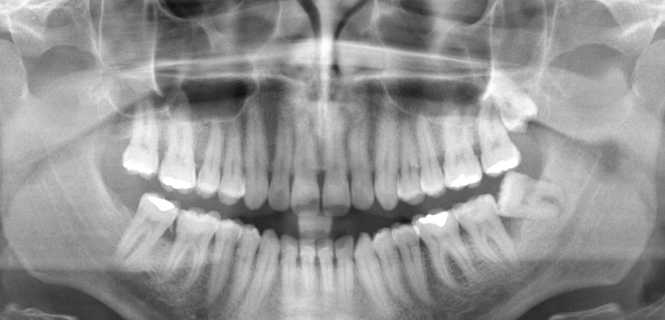

Pantomogram, znany również jako panorama lub zdjęcie RTG pantomograficzne, to podstawowe narzędzie diagnostyczne wykorzystywane w stomatologii. Dzięki niemu dentyści mogą uzyskać kompleksowy obraz stanu zdrowia jamy ustnej pacjenta. Uwidaczniają wówczas zarówno zęby, jak i struktury kostne szczęki oraz żuchwy. Badanie pantomograficzne stanowi nieocenione wsparcie w planowaniu leczenia dentystycznego oraz monitorowaniu postępów terapii. Pomaga również ortodontom przygotowującym pacjentów do założenia aparatu, a także protetykom, którzy wykonują protezy zębowe i odbudowują zęby na implantach.

Pantomogram to zdjęcie RTG warstwowe szczęki i żuchwy. Umożliwia jednoczesne obrazowanie zębów, szczęki, żuchwy oraz większej części zatoki szczękowej, podniebienia twardego, a także stawów skroniowo-żuchwowych. Zajmuje ok. 15 sekund, a jego wyniki są dostępne już po kilku minutach od przeprowadzonej procedury.

Dzięki niemu możliwe jest ustalenie prawidłowej anatomii i wykrycie patologii w obrębie jamy ustnej. Specjalista porównuje prawą i lewą stronę szczęki i na tej podstawie stwierdza, czy w którymś obszarze widoczne są zmiany. Bierze wówczas pod uwagę takie aspekty jak m.in. lokalizacja wykrytych zmian anatomicznych, a także ich kształt i rozmiar oraz wewnętrzna struktura.

Na podstawie uzyskanych danych specjalista może ocenić np. jak wiele zębów zostanie zaatakowanych przez próchnicę. Dzięki temu łatwiejsze staje się ułożenie odpowiedniej strategii leczenia. Zwiększają się też szanse na sukces planowanej terapii. Należy mieć jednak na uwadze, że nie tylko lekarze stomatologii zachowawczej korzystają z badania pantomograficznego. Wykonują je także ortodonci przygotowujący pacjenta do leczenia ortodontycznego oraz protetycy wykonujący protezy zębowe i odbudowujący zęby na implantach.